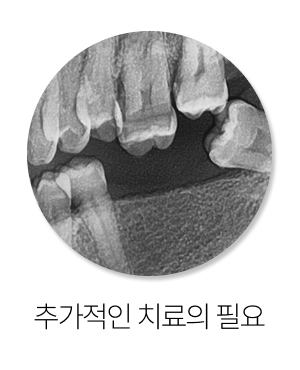

셋째, 추가 치료 가능성이 생깁니다.

원래는 빠진 부위만 회복하면 될 문제였는데, 치아 이동이 심하면 보철이나 잇몸치료, 경우에 따라서는 교정적 접근까지 함께 고민해야 하는 상황이 생기기도 합니다.

즉, 처음에는 간단했을 문제가 나중에는 더 복합적인 치료 계획으로 이어질 수 있다는 뜻입니다.